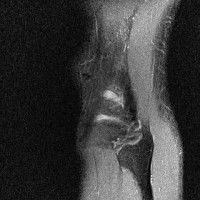

무릎 mri 간단히 봐주실 수 있으시나요 ㅠㅠ

안녕하세요 8년전 십자인대 수술하고 최근 무리한 운동에 무릎 불편감이 생겨서

mri 찍었습니다.

진단결과는 첫 찍은 병원에서 활액막염 이라는 진단을 받았습니다. 혹시 봐주실 수 있으실까요?

올라온 MRI가 단편적이라서 정확한 진단에 어려움이 있지만 십자인대에는 큰 이상이 있지는 않은것 같으며, 무릎관절내 물이 있는 것으로 보아 활액막염의 진단이 맞을 것 같습니다.

하지만 단편적인 영상이기 때문에 촬영병원에서 정확한 판독지 등을 받으시는 것이 좋겠습니다.